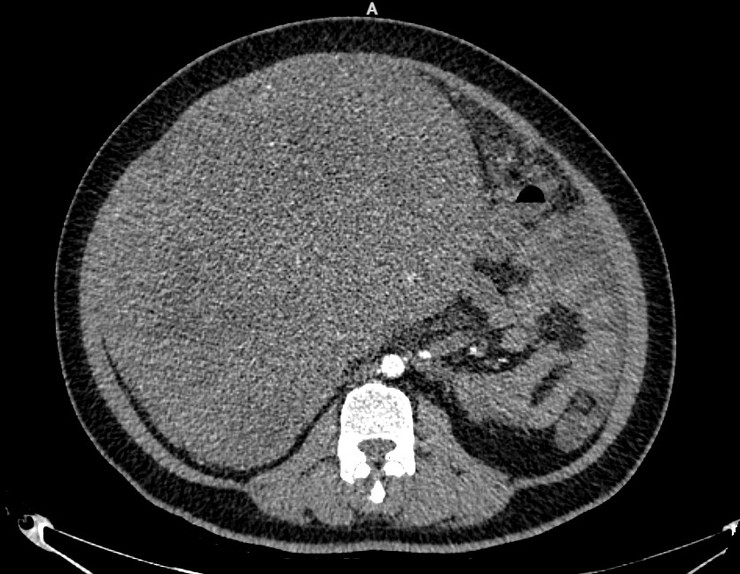

Kết quả chụp cắt lớp vi tính cho thấy khối u lan tỏa vùng hạ sườn phải, quanh rốn và hạ vị với kích thước lên tới 22,7 x 29 cm, bờ không đều. Khối u tiếp xúc và chèn ép nhiều cơ quan như gan, túi mật, thận phải, tụy, đồng thời dính với đáy tử cung. Ngoài ra, bệnh nhân còn có tình trạng dịch ổ bụng nhiều và tràn dịch màng phổi hai bên.

Hình ảnh phim chụp cho thấy khối u chiếm toàn bộ ổ bụng. (ảnh BV)